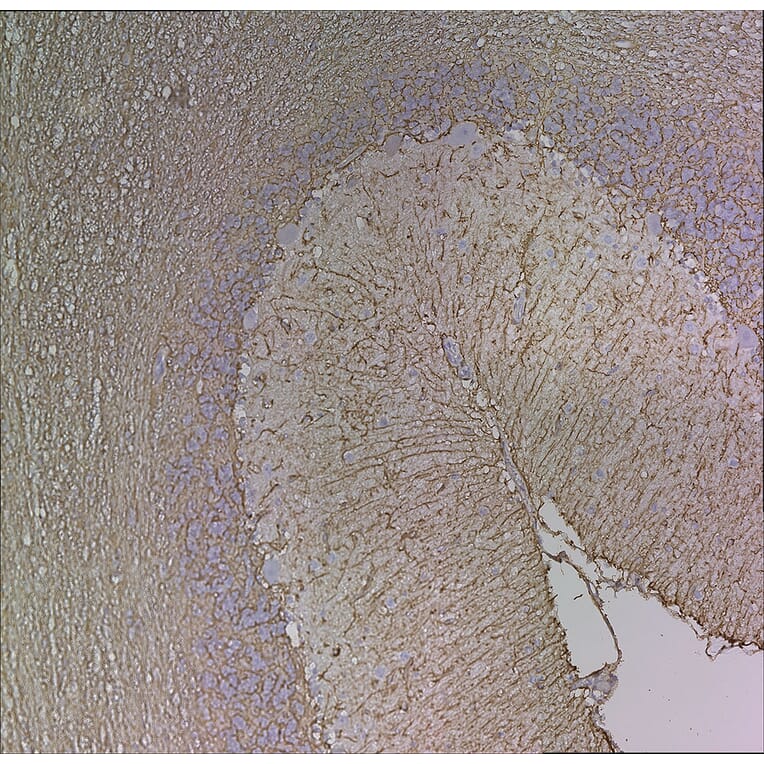

Immunohistochemistry analysis of paraffin embedded formalin fixed human cerebellum stained with Anti-GFAP Antibody [5C10] (A85422). The folds of the molecular layer are at the right and granular and white matter layers are on the left. Counterstained with Hematoxylin (blue).

Immunohistochemistry analysis of formalin fixed paraffin embedded adult horse brain samples removed whole, sliced incompletely cross ways and fixed over a 10-20 day period. The whole brain was put in a large necropsy specimen bucket containing 1-2 gallons of fixative, and after 24 hours, the formalin was poured off and then fresh formalin was added. The samples were fixed and embedded in paraffin in 2007 and sections were kept at room temperature until 2011. The sections were processed for antigen retrieval by boiling in Citrate buffer, pH 6, for 10 min. Primary incubation with Anti-GFAP Antibody [5C10] (A85422) was for 1 hour at 37°C, and secondary antibody incubation and color reaction was performed using the Vector mouse ABC kit.